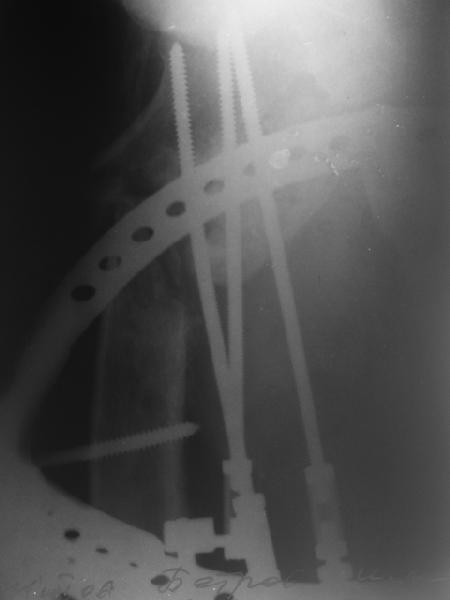

Leonid Solomin 03 Март 2009, 22:07

Уважаемый Попов Виктор!

Возможно, пример (в приложении) поможет Вам определиться с выбором тактики лечения (у нашего пациента, кроме тугого ложного сустава вертельной области, сложная деформация н/3 бедренной кости; т.к. это не имеет значения к обсуждаемой теме - оставил "за кадром"). Как Вы видите, мы в данном случае не вводили чрескостные элементы в зону установки имплантата. При отказе от наложения опоры на таз (кстати, она не обязательно может быть громоздкая спицевая; арки со стержнями-шурупами, введенными в крыло подвздошной вполне достаточно) "не удивляйтесь", если опора со стержнями-шурупами, введенными в вертельной области в скором времени дестабилизируется, возникнет воспаление мягких тканей у чрескостных элементов. Такая опора "имеет на это право": нагрузка конечности от вершины дистального фрагмента до кончиков пальцев ляжет на нее. А двух-трех введенных рядом стержней-шурупов, как их не разноси от фронтальной плоскости, в данном

случае явно недостаточно для адекватной фиксации. + для того, чтобы выбрать оптимальные чрескостные элементы для промежуточной и дистальной опор, можете воспользоваться атласом